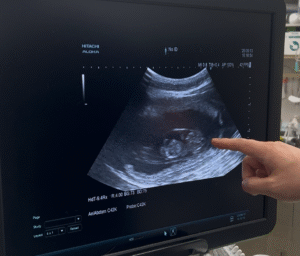

新しい命を授かりました 2025 9/13 NEWS 2025-09-13 JUJU、新しい命を授かりました。 出産予定日10月中旬 MOANA、新しい命を授かりました。 出産予定日10月初旬 NEWS この記事が気に入ったら フォローしてね! Follow Me よかったらシェアしてね! URLをコピーしました! URLをコピーしました! コメント コメントする コメントをキャンセルコメント ※ 名前 ※ メール ※ サイト 次回のコメントで使用するためブラウザーに自分の名前、メールアドレス、サイトを保存する。 上に表示された文字を入力してください。